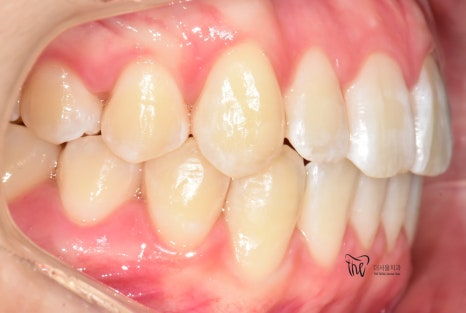

먼저, 임상 사진 5장을 보여드립니다.

그냥 겉으로 봤을 때는 단순 치아들의 불규칙성

때문에 치과에 내원을 하신 것으로 볼 수 있습니다.

그러나, 좌측에서 바라봤을 때는 어금니들이

부정교합을 띄고 있는 것을 볼 수 있습니다.

즉, 거꾸로 물리는 반대교합의 양상을 보여주고

있고 이런 증세 때문에 턱관절의 통증까지도

같이 느끼고 있는 채로 내원을 하셨습니다.

즉, ‘턱관절 통증 치료 및 치열의 개선’

이 2가지를 함께 치료를 받고 싶어서 먼 길을

걸어서 오셨던 환자의 임상 증례입니다.